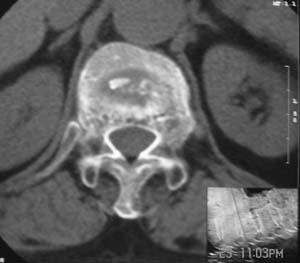

患者,女,72岁,胸背部疼痛3月余,无明显外伤史。曾应用局部封闭、非甾体类止痛药治疗效果不明显,近来疼痛缓解频感背困,平卧缓解,近日行ct检查发现胸12椎体病变,烦请同道发表意见,诊断什么?有何治疗经验!谢谢!!!

标绘图示:第十二胸椎级第一腰椎椎体楔形改变。ct扫描示:第十二胸椎椎体骨质结构紊乱,并可见一囊状低密度影,边缘可见硬化,椎体皮质完整。

考虑:第十二胸椎陈旧性骨折、许莫氏结节。